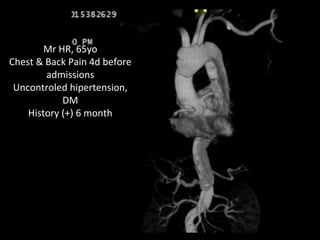

Mr HR, 65yo

Chest & Back Pain 4d before

admissions

Uncontroled hipertension,

DM

History (+) 6 month